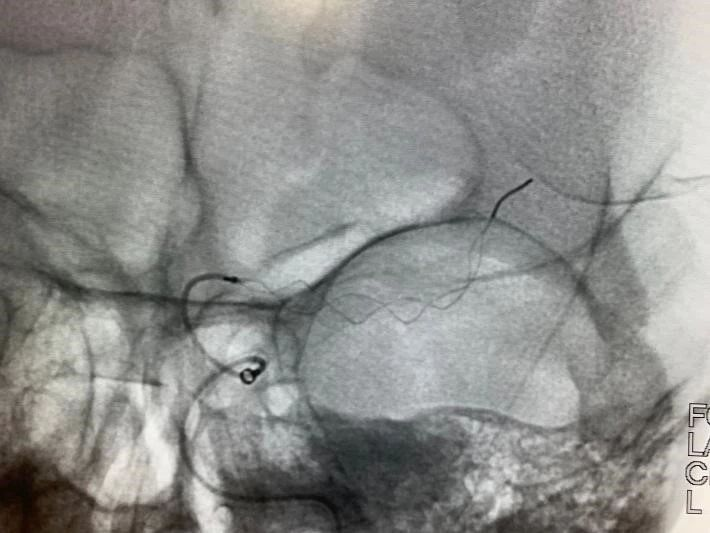

患者发病到入院时间超过4.5h时间,静脉溶栓时间窗超过,考虑大血管病变,患者急诊CT提示左侧大脑中动脉高密度征,ASPECTS评分9分,未见明显低密度灶,结合患者急诊查体,高度提示左侧颈内动脉系统大动脉闭塞。与家属沟通后,急诊行DSA,必要时予血管内治疗。

急诊头颅CT:左侧大脑中动脉高密度征,

ASPECT评分:9分。